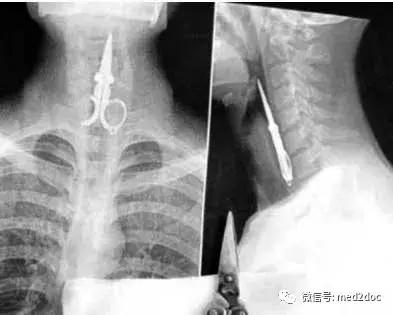

X光下很难以想像这把剪刀是如何进入喉咙的